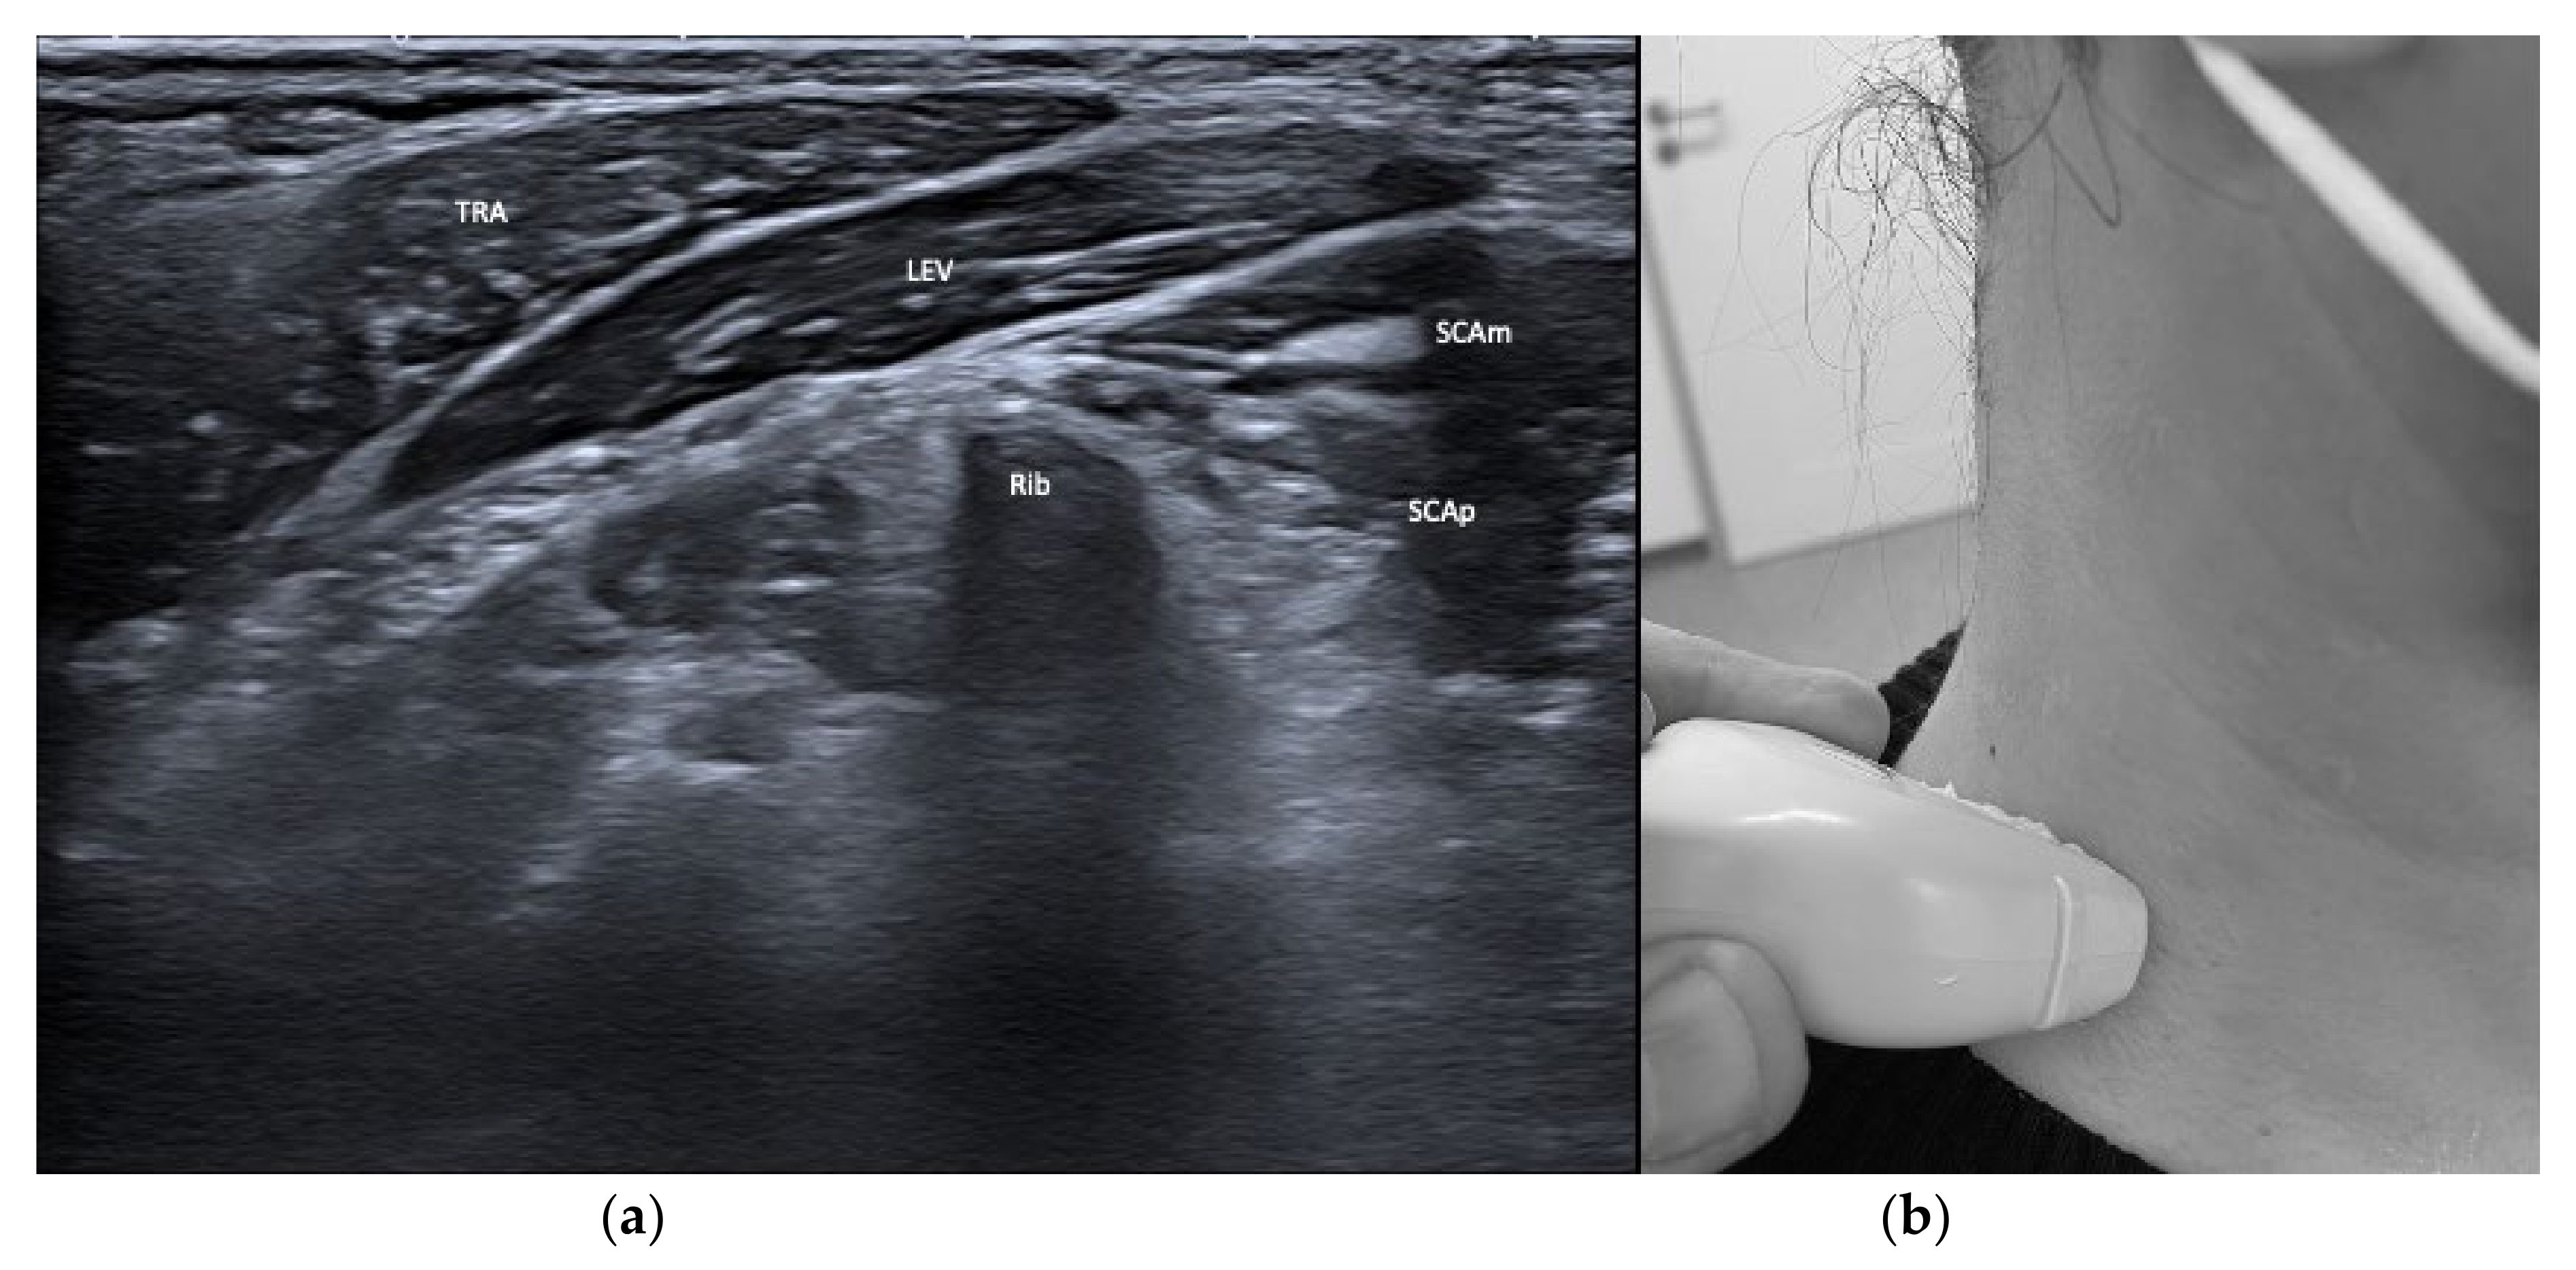

| Splenius cervicis (SPLcer) | Ipsiversion of neck | +++ | ++ | LEV, TRA, Longissimus cervicis | Relevant for full turn of the neck |

| Trapezius (TRA) | Extension of neck | + | + | LEV, Supraspinatus | |

| Levator scapulae (LEV) | Lift of scapula | + | + | SPLcer, TRA | |